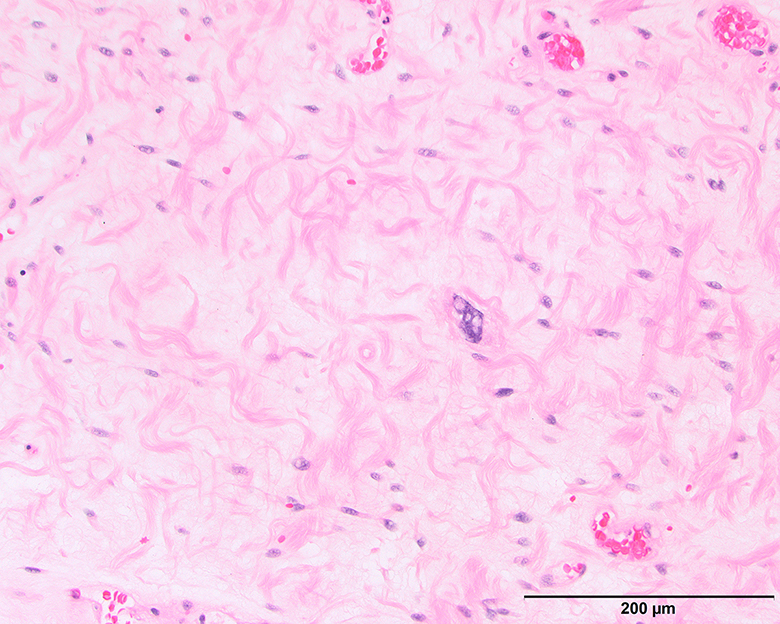

Microscopic (histologic) description

- Depends on subtype, generally composed of mature fat with variably sized adipocytes and bands of fibrotic stroma containing spindle cells with enlarged, hyperchromatic nuclei

- Can be markedly atypical

- Cellularity is low and mitotic figures are uncommon

- Atypical cells are more commonly found in fibrous septa and in a perivascular distribution

- Lipoma-like subtype

- Most common subtype

- Scattered atypical cells may be diffuse or exceedingly rare

- Frequently contains lipoblasts

Microscopic (histologic) images

Contributed by Michael Clay, M.D., Melanie Bourgeau, M.D. and AFIP

Morphologic variability: